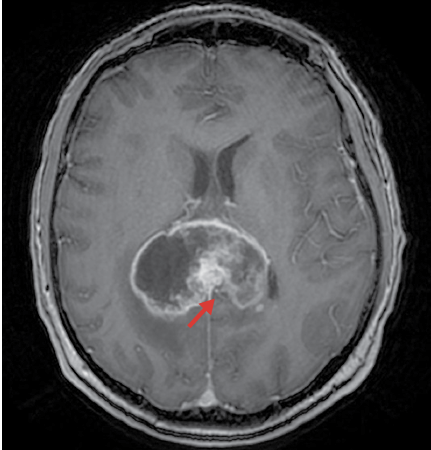

Histologic features of

Glioblastoma

Glioma with WHO grade IV

A

Glioblastoma [13]

Glioblastoma [13d]